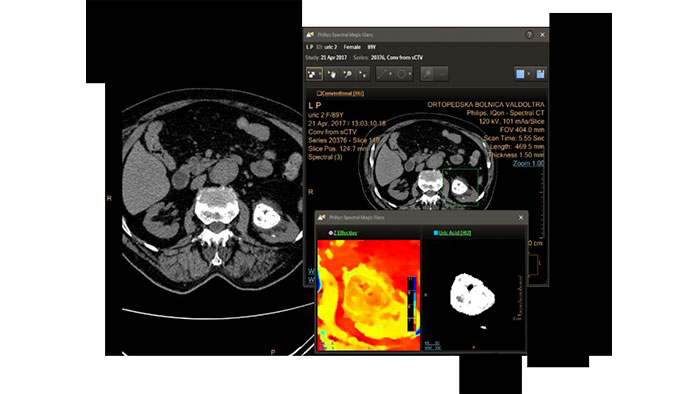

Review spectral data in a range of not spectral-enhanced CT applications

Allows retrospective use of spectral data that was saved in a series of spectral base images (SBI). The fast launch of LMG allows review and identification of the most relevant results to be launched into the application for further analysis.

IQon Spectral CT* Functionality

The spectral viewer is optimized for analysis of spectral data sets from the IQon Spectral CT Scanner. Obtain a comprehensive overview of each patient quickly and easily, quantify quickly, and assist in diagnosis. It is designed to accommodate general spectral viewing needs with additional tools to assist in CT images analysis.